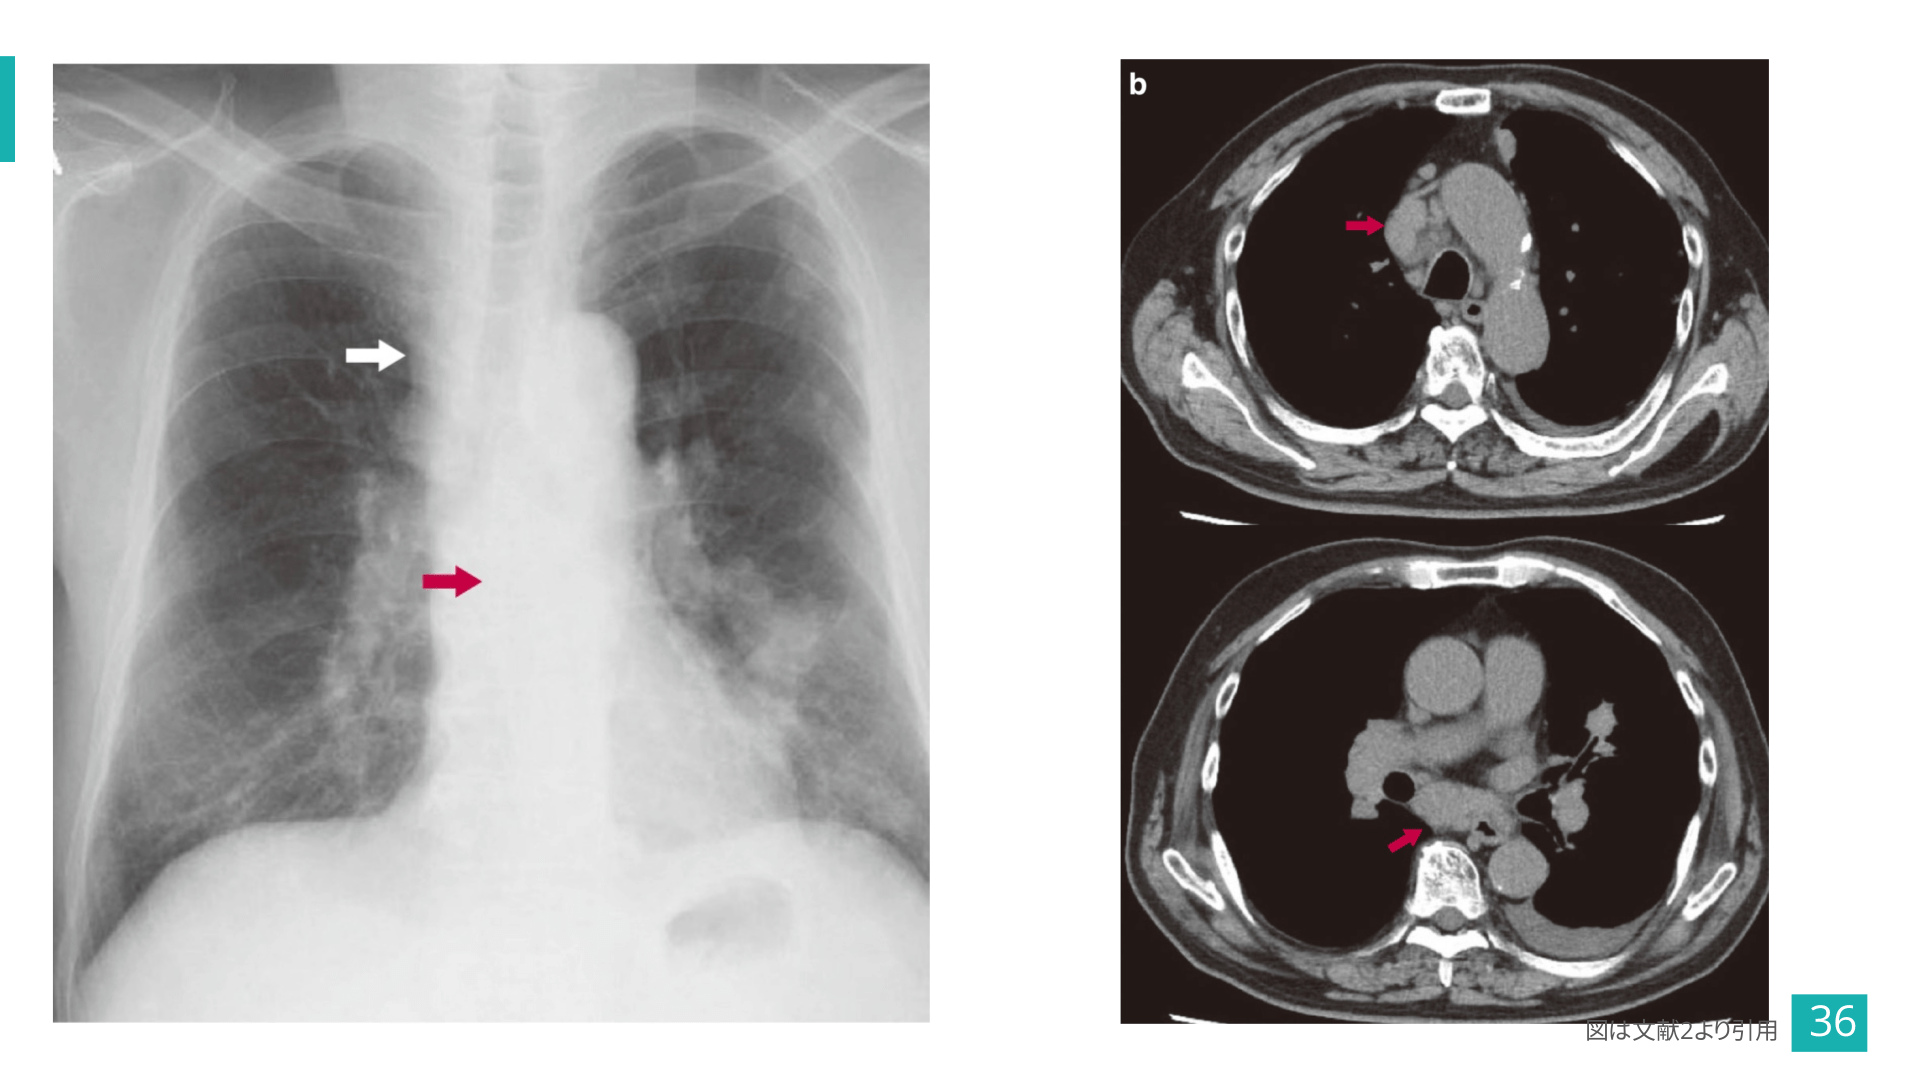

#37.

気管分岐下リンパ節腫大 図は文献2より引用 37

奇静脈食道線の偏位③ 図は文献2より引用 35

#36.

図は文献2より引用 36